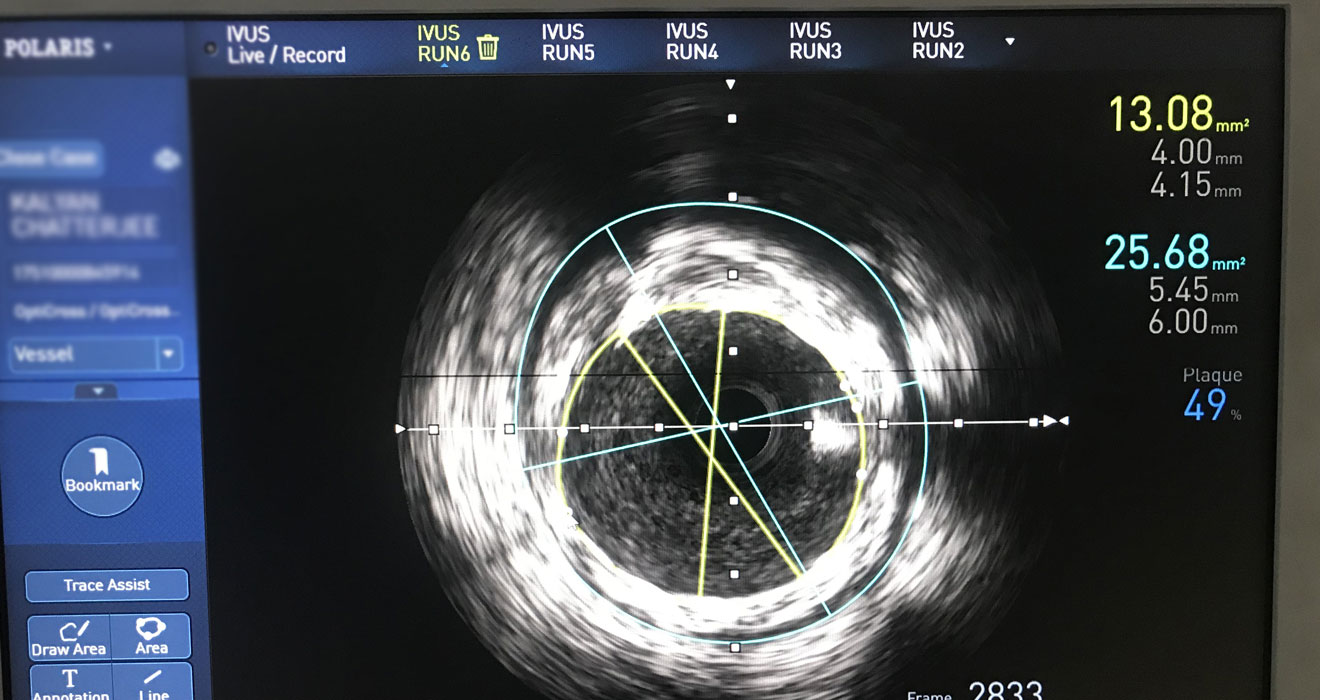

Advance Coronary Imaging